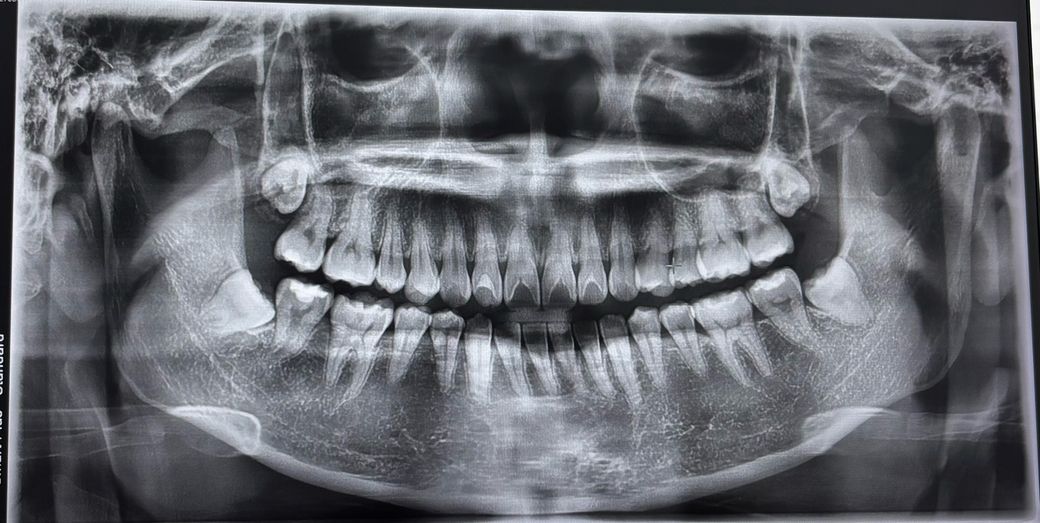

저 같은 경우는 사랑니 빼야하나요??

사랑니를 꼭 빼야하나요? 아프지도 않고 지금까지 그냥 아무 이상 없었는데 치과 가서 뽑는 건가요? 4개 다 빼야하나요? 안 뽑아도 크게 문제되지 않으면 안뽑고싶은데요

• 1번 째 사진

아래 사랑니 2개 경사져 있어 바로 앞 어금니 상하게 하니 가능한 빨리 빼는 것은 추천합니다. 윗쪽 사랑니 2개는 깊이 매복되어 있으니 그냥 두거나 조금 더 기다렸다가 더 내려오는 뽑아야 합니다.

완전히 뼈에 파묻혀 있는 완전 매복 사랑니의 경우 뺄지 말지는 본인 선택이고, 평상시 양치질 등 구강위생관리가 잘 되고 있다면 굳이 빼지 않아도 됩니다